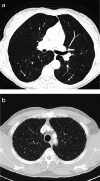

Objectives: Pulmonary Langerhans cell histiocytosis (PLCH) is a rare interstitial granulomatous disease that usually affects young adults who are smokers. Chest computed tomography (CT) allows a confident diagnosis of PLCH only in typical presentation, when nodules, cavitated nodules and cysts coexist and predominate in the upper and middle lungs.

Methods: This article includes a pictorial essay of typical and atypical presentations of PLCH at initial chest CT. Various appearances of PLCH are illustrated and possible differential diagnosis is discussed.

Results: PLCH can present with some aspecific features that may cause diagnosis of the initial disease to be overlooked or other pulmonary diseases to be suspected. In cases of nodule presentation alone, the main differential diagnosis should include lung metastasis, tuberculosis and other infections, sarcoidosis, silicosis and Wegener's disease. In cases of cysts alone, the most common diseases to be differentiated are centrilobular emphysema and lymphangiomyomatosis. Clinical symptoms are usually non-specific, although a history of cigarette smoking, coupled with the presence of typical or suggestive findings at imaging, is key to suspecting the disease. Atypical presentations require surgical biopsy for diagnosis.

Teaching points: • PLCH is a rare interstitial smoking-related disease that usually affects young adults. • The typical first CT shows a mix of nodules, cavitary nodules and cysts in the upper-middle lungs. • Atypical appearance, either cysts or nodules alone, mandates that other diagnoses be considered. • Lung cystic involvement correlates with lung function abnormalities and predicts functional decline. • Integration of the clinical history and imaging results is key to diagnosis.